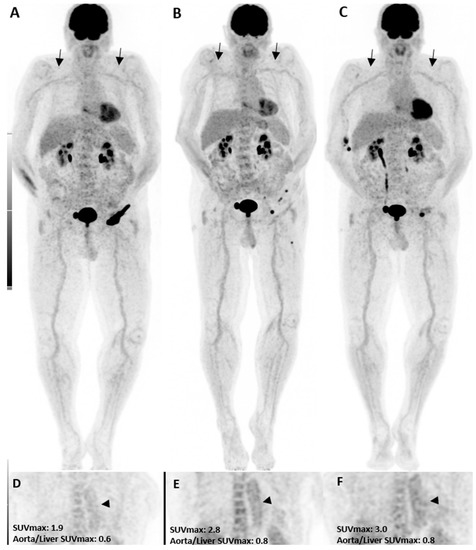

In the pre-treatment [18F]FDG PET/CT, three patients had grade 2 uptake in the thoracic aorta, while only one had a grade 2 uptake in the abdominal aorta and subclavian artery. Three months after treatment, grade 2 uptake was increased in all vascular territories (Figure 1). The thoracic aorta showed the highest amount of grade 2 uptake in our study in all [18F]FDG PET/CT images and was considered for statistical analysis. While only three patients had a grade 2 uptake in the initial [18F]FDG PET/CT (PET1), it was increased to five after three months and further increased to twelve patients (seven new cases) six months after immunotherapy. Although the rise was statistically insignificant three months after therapy, it became significant at six months (p-value = 0.01). Interestingly, in those seven new patients with visual presentation of inflammation in the third scan, five presented with other irAEs in the follow-up, including colitis, neuritis, hypophysitis, pneumonitis, and bullous pemphigoid, resulting in therapy termination. One patient discontinued therapy due to a personal request. Moreover, three of those five patients with grade 2 uptake in both PET2 and PET3 showed early disease progression thereafter, and the treatment was discontinued.

Figure 1.

A patient with the diagnosis of melanoma with ongoing immune checkpoint inhibitors treatment without a history of cardiovascular diseases or clinical evidence of vasculitis. [18F]FDG PET/CT maximum intensity projections (B,C), as well as coronal (E,F) views, three and six months after treatment initiation, are shown. The mild increase in uptake intensity of the aorta and subclavian arterial walls was visually seen compared to the pretreatment (A,D, arrows) images. Semi-quantitative analyses by SUVmax were correlated with visual findings showing a mild increasing pattern of [18F]FDG uptake suggestive of immunotherapy-related mild arterial wall inflammation.